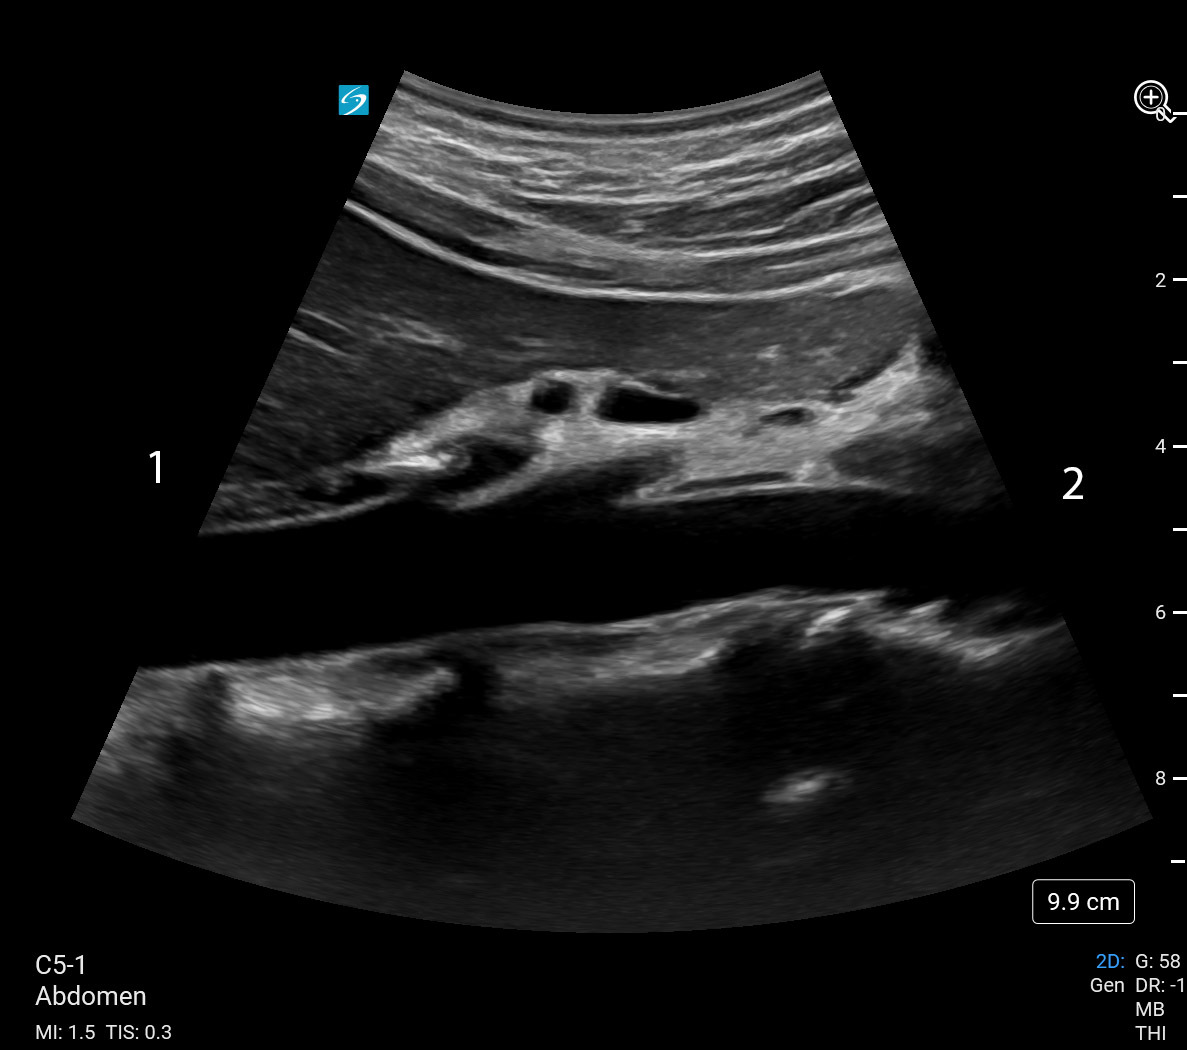

Aorta Longitudinal (Sonosite PX C5-1) Image

Towards Patient's Head

Towards Patient's Feet